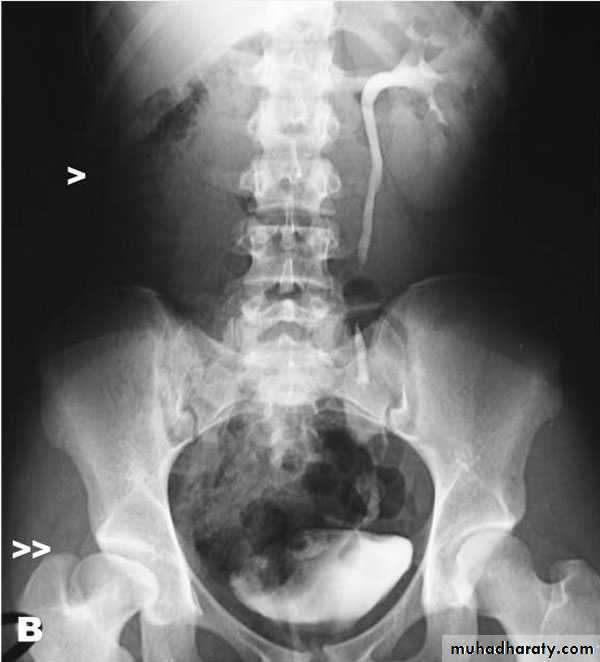

Bladder rupture. A cystogram done in a patient after a motor vehicle accident shows extravasation of contrast (arrows) into the tissues surrounding the bladder, an extraperitoneal bladder rupture